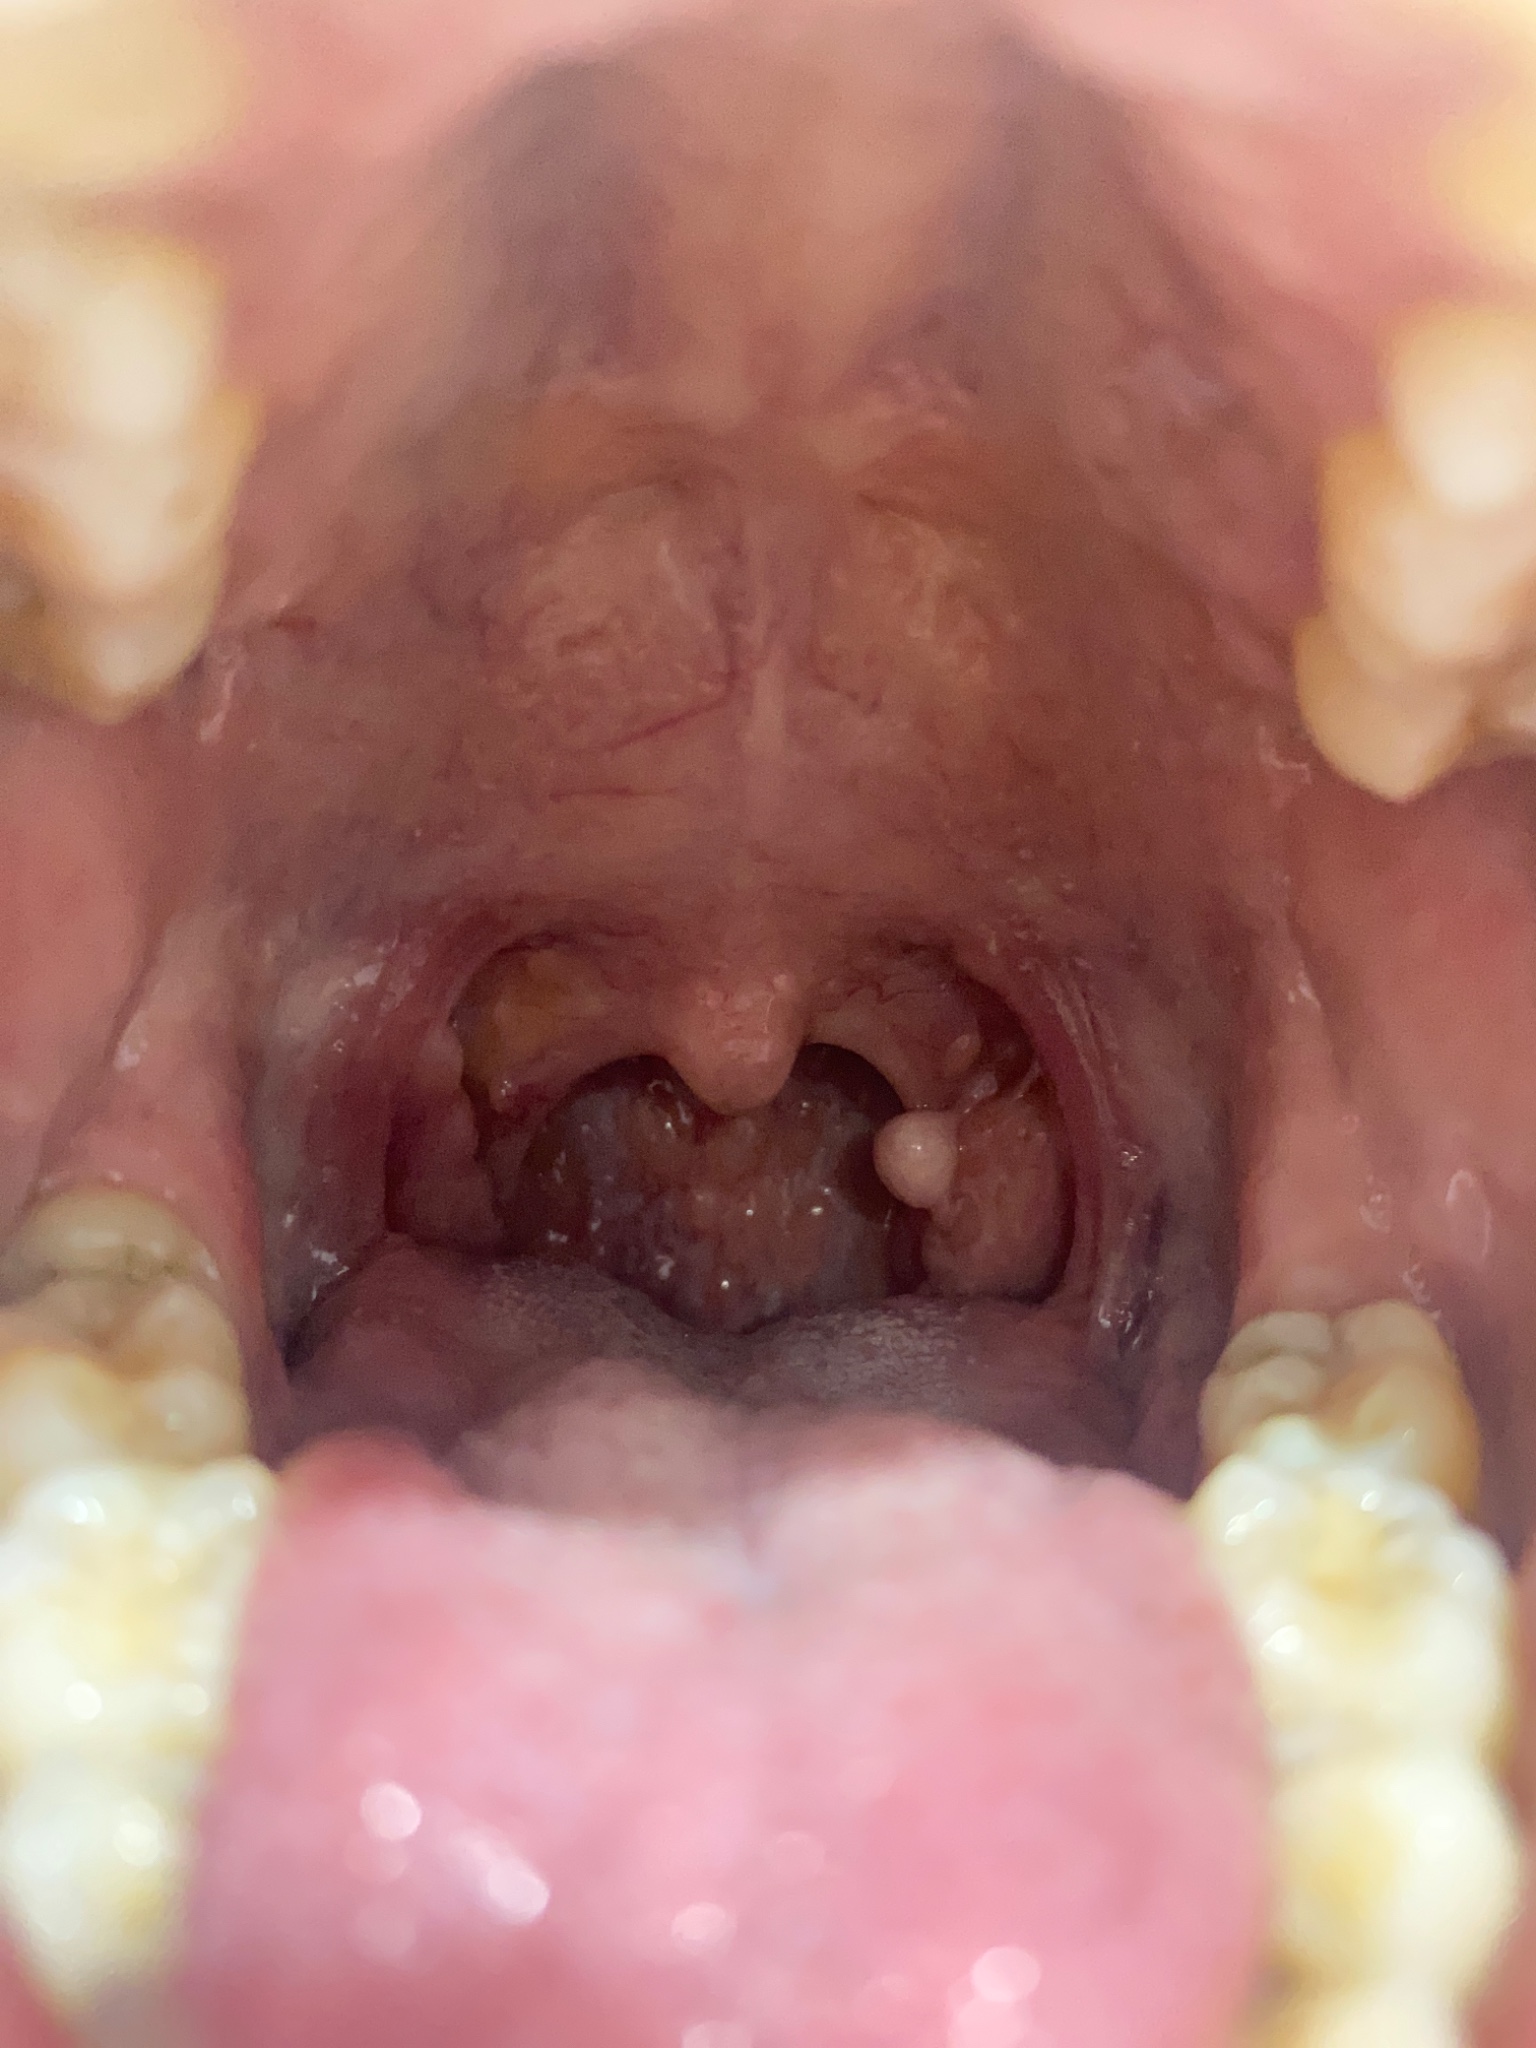

สวัสดีค่ะ ขออนุญาตสอบถามเกี่ยวกับปัญหาช่องปากค่ะ

พอดีหนูมีติ่งเนื้อตรงทอนซิลค่ะ กังวลมากค่ะ มีใครพอจะทราบมั้ยค่ะ ว่าคืออะไร